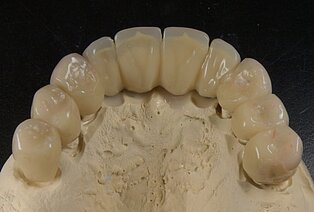

Meisterarbeit von Peter Dengel